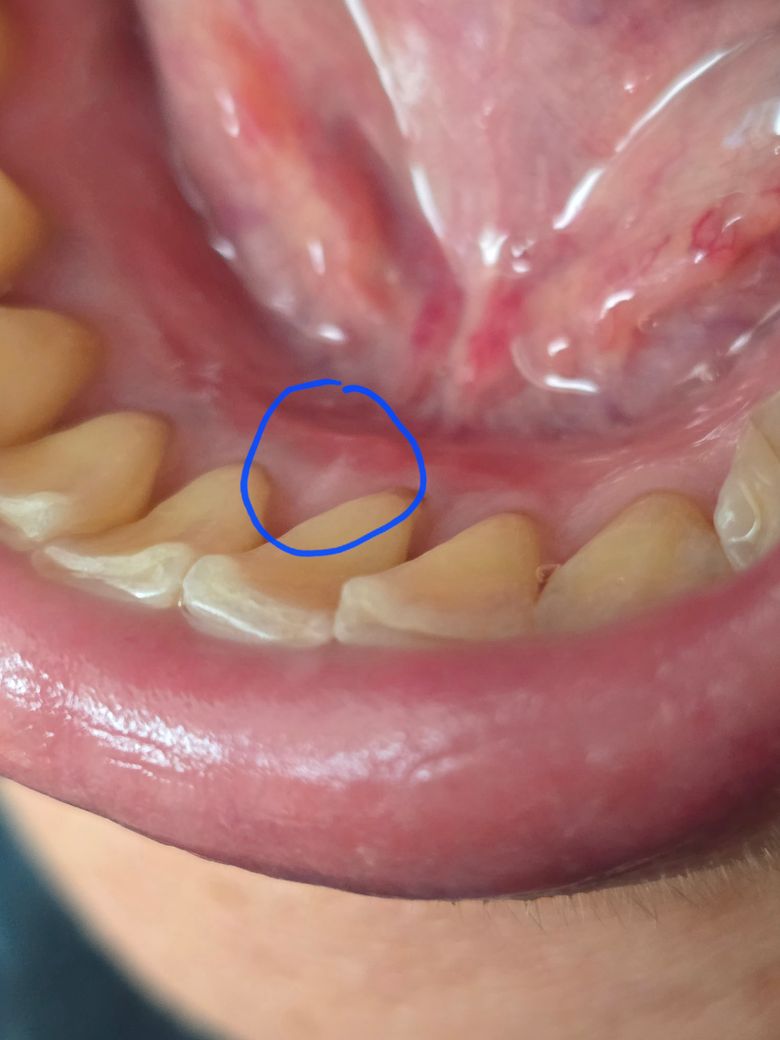

잇몸에 흰반점이 있는데 무엇인지 궁금합니다.

잇몸에 구내염이 생겨 관찰하다

흰반점이 있는걸 보았습니다.

그다음날 조금 줄어들더니

일주일후 지금 잔흔이 조금 남아있습니다 무엇인가요?

저부위는 치석이 잇는거 같습니다. 치과에 가셔서 검진후에 스켈링을 받으시면 없어질것같습니다.

사진으로 볼 때는 정상적인 잇몸 조직으로 보입니다. 치아 주변의 잇몸은 살짝 흰색으로 보이는 경우가 있습니다.

흰반점이 생기고 시간이 지나면서 감소했다면, 이는 흔히 볼 수 있는 아프타성 구내염일 가능성이 높습니다. 증상이 거의 없었기에 특별한 치료가 필요로 되지 않으며, 잔흔이 커지거나 통증이 재발하면 치과 진료를 받길 권합니다.